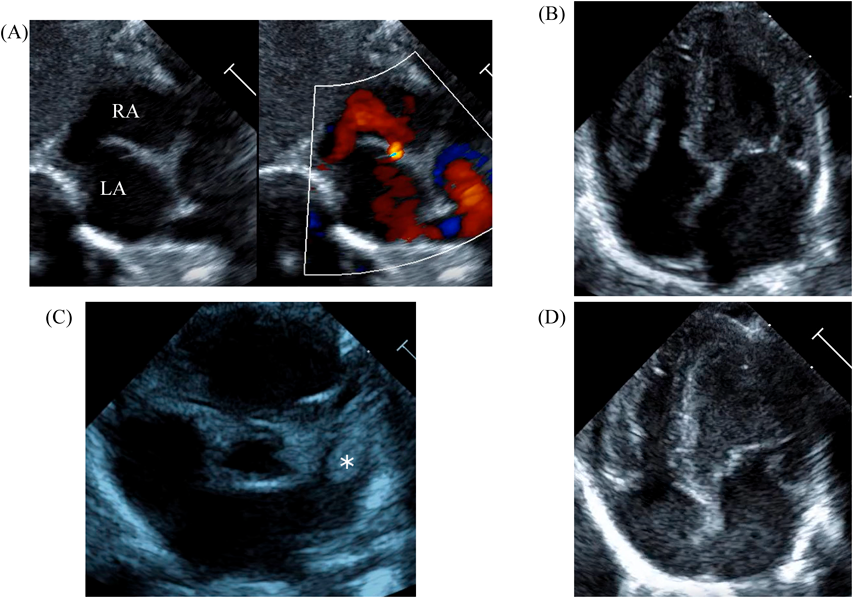

LV ejection fraction was down to 40% with moderate mitral regurgitation, whereas RV contractility was preserved. The biventricular volumes seemed well-balanced, and the LV end-diastolic diameter (15.9 mm) was within the normal range. Systolic RV pressure was estimated as 70 mmHg by regurgitation flow across the tricuspid valve (velocity 4.1 m/s), indicating persistent pulmonary hypertension. The ductus arteriosus had already closed. The foramen ovale (FO) was patent with very little blood flow through (Fig. 1A). The left atrium (LA) was dilated and non-contractile (Fig. 1B, Supplementary Video S1). Echocardiography showed a highly echogenic mass measuring 10×5 mm in the LA appendage, which was not mobile. The mass was suspected to be a thrombus (Fig. 1C, Supplementary Video S2). Blood tests indicated a high B-type natriuretic peptide (BNP) level (1,102.8 pg/mL) and a mildly elevated D-dimer level (2.27 µg/mL). There was no decrease in platelet count (279×103 /µL) or increase in clotting time (prothrombin time/international normalized ratio: 1.05, activated partial thromboplastin clotting time [APTT]: 29.9 s). The levels of fibrinogen (326 mg/dL), antithrombin-III (65%), protein C (35%), and protein S (68%) were within normal limits for neonates. There was no maternal history of systemic lupus erythematosus or antiphospholipid antibody syndrome, which could have affected neonatal formation of intracardiac thrombi.

Fig. 1 Echocardiographic findings

(A) Echocardiography at the time of admission (subcostal view) showed only a small slit-like blood flow across the foramen ovale. (B) Echocardiography on admission (four-chamber view) showed a dilated left atrium with an end-systolic volume of 4.0 mL. The left ventricular end-diastolic diameter was normal (15.9 mm). The left ventricular contraction was mildly reduced, with an ejection fraction of 40%. (C) Echocardiography on admission (short axis view) showed a highly echogenic and non-mobile mass (white *) of 10 mm ×5 mm in the left atrial appendage. (D) Echocardiography on day 9 showed improvement in left ventricular contractility. Atrial size had become normal, with a left atrial end-systolic volume of 2.1 mL. LA, left atrium; RA, right atrium.

We administered diuretics as well as continuous infusion of olprinone and unfractionated heparin. Continuous infusion of heparin was started at 10 U/kg/hr and gradually increased to 20 U/kg/hr, but the APTT was only slightly prolonged to 36.0 seconds on day 9. Daily echocardiography showed gradual improvement in LV function. Olprinone and diuretics were discontinued by day 9, because the LV ejection fraction improved to 65% and the LA size normalized (Fig. 1D, Supplementary Video S3). Marked mobility of the mass appeared in parallel with the restoration of LA contractility on day 10 (Supplementary Video S4). We performed a surgical thrombectomy on cardiopulmonary bypass so as to avoid systemic embolism. A white structure adhering to the LA appendage was excised (Fig. 2A), and pathological diagnosis was a calcified thrombus (Fig. 2B). The postoperative course was uneventful. Low-dose aspirin was started on the 3rd postoperative day. The patient was followed up on an outpatient basis, and aspirin was discontinued at 4 months postoperatively. At the time of this publication, the patient is 2 years old, and she has experienced no recurrent clots or embolic episode thus far.